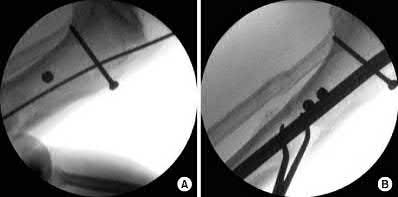

Figures A and B demonstrate a distal third tibial shaft fracture with simple intra-articular extension. The axial and coronal CT cuts in Figures C and D further clarify the articular injury. Illustrations A and B demonstrate a comminuted distal third tibial fracture with simple intra-articular extension. Illustrations C and D are fluoroscopic images of the same injury after intramedullary nailing and percutaneous fixation of the articular component.

A 25-year-old female is involved in a motor vehicle collision. She presents with the isolated injury seen in Figures A through D. Her leg is swollen but her skin is intact. She has no clinical signs of compartment syndrome. Which of the following treatment options will allow for maintenance of fracture alignment and minimize the risk of soft tissue complications?

The patient presents with a closed distal third metaphyseal-diaphyseal distal tibia fracture with simple intra-articular extension. Immediate intramedullary nailing along with percutaneous fixation of the articular component provides appropriate restoration of length, rotation and alignment and minimizes the risk of wound complication.

Displaced distal third tibia fractures may be associated with simple intraarticular extension. Operative treatment of intra-articular distal tibia fractures has historically been performed with open reduction and internal fixation. Early open reduction and plate fixation of pilon fractures has been associated with high rates of infection and wound complication. In select patterns with simple articular extension, percutaneous screw fixation and medullary nailing may provide appropriate reduction with minimal soft-tissue risk.

Marcus et al. evaluated the outcomes of immediate intramedullary nailing and percutaneous fixation of simple intra-articular distal tibia fractures (AO/OTA 43 C1 and C2). The authors found excellent rates of union and alignment, however caution against broad application of this technique until more rigorous randomized studies can be performed.

Sirkin et al. retrospectively evaluated the results of a staged approach to management of intra-articular distal tibia fractures with temporary bridging external fixation followed by open reduction and internal fixation (ORIF). The authors found decreased rates of wound complication and infection compared with prior studies.

Incorrect Answers:

Answer 1: Closed reduction and casting of this injury results in increased rates of malalignment

Answers 2 and 5: Immediate open reduction of pilon fractures has historically been associated with high rates of infection and wound complications

Answer 4: This fracture pattern would be difficult to control with a uniplanar fixator. A circular or multiplanar fixator would be a potential treatment option